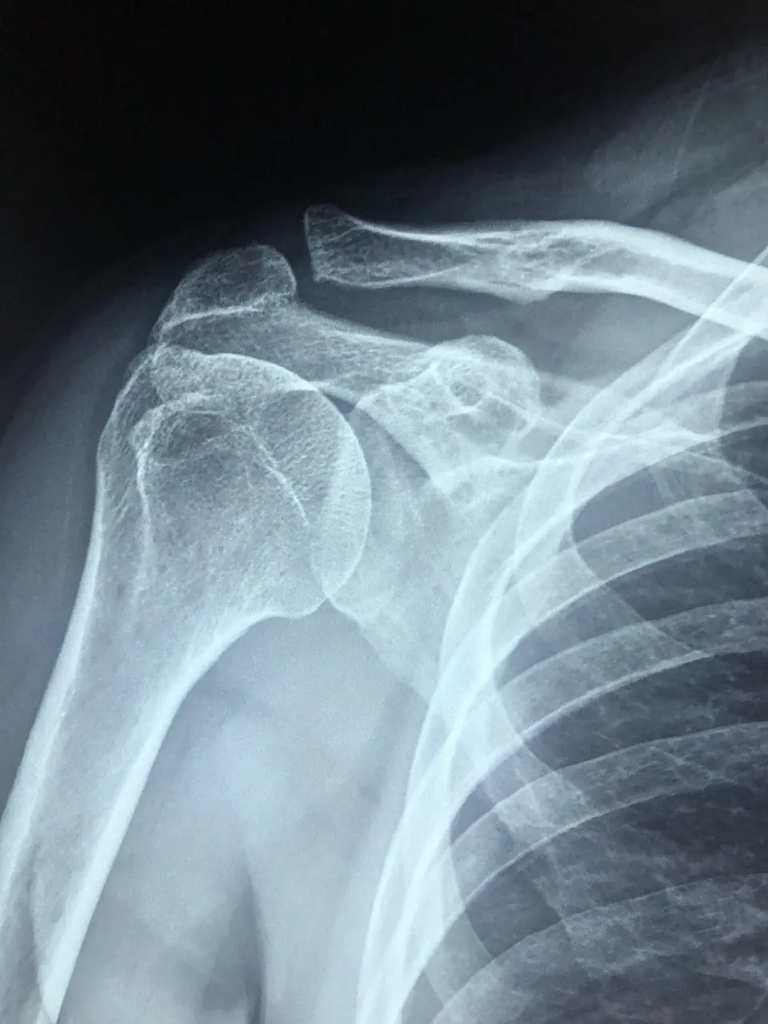

The glenohumeral (shoulder) joint and the scapulothoracic articulation must move in concert; the scapula should upwardly rotate and stabilize as the arm lifts to enable safe, efficient overhead motion.

It's the coordinated movement between the scapula and the humerus during arm elevation, typically with about a 2:1 ratio of glenohumeral elevation to scapular rotation.